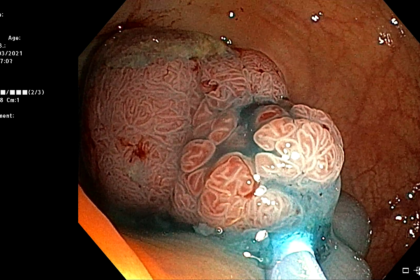

Les anomalies détectées lors d’une coloscopie peuvent être une excroissance de tissus nommés polypes, de diverticules (hernies), la présence de tissus lisses d’aspect anormal ou une inflammation. L’analyse des prélèvements au microscope permettra de poser le diagnostic. La présence d’anomalies n’indique pas nécessairement qu’il s’agisse d’un cancer, la majorité des polypes étant bénins ; néanmoins, leur élimination permet de prévenir l’apparition de la maladie.

Une fois sous anesthésie générale, le coloscope est introduit par l’anus puis progressivement amené jusqu’au côlon. Afin de déplisser les tissus, le côlon est gonflé par de l’air permettant ainsi une bonne visualisation de toutes les parois. Au fur et à mesure de la progression du coloscope, des images sont directement transmises et analysées par le gastroentérologue. Si des anomalies sont détectées, un échantillon de tissu est prélevé pour analyse ultérieure (biopsie). Il est également possible que l’intégralité du tissu anormal soit enlevée (ablation).